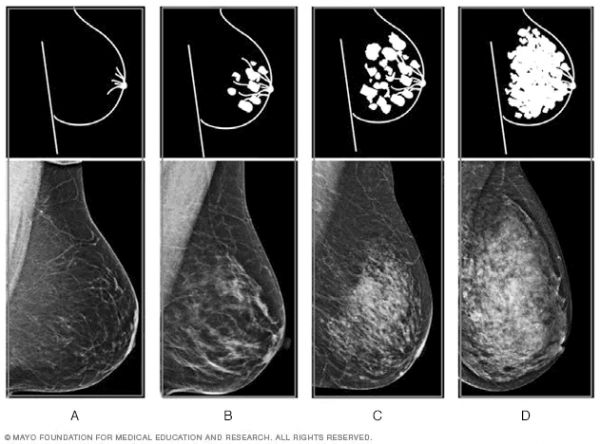

在美国,X线是乳腺癌筛查最主要的影像学方法。乳腺X线检查中,脂肪组织容易透视,呈深色透明状;纤维腺体组织难以透视,呈白色区域。因此放射科医生可以使用以下4种分类,描述女性的乳腺密度:

A)脂肪型:乳房几乎全由脂肪构成;

B)散在纤维腺体型:大部分乳腺是非致密的,存在一些分散的致密区域;

C)不均匀致密型:大部分乳腺是致密的,存在一些分散的非致密区域;

D)极度致密型:乳房几乎全由纤维腺体组织构成。

乳腺密度的4种水平丨mayoclinic.org